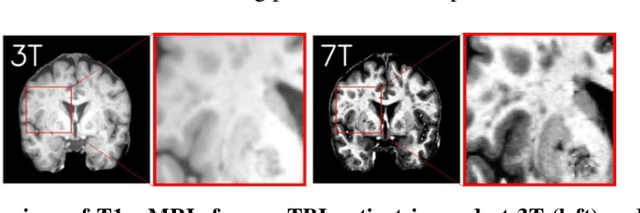

Abstract:Supervised deep learning techniques can be used to generate synthetic 7T MRIs from 3T MRI inputs. This image enhancement process leverages the advantages of ultra-high-field MRI to improve the signal-to-noise and contrast-to-noise ratios of 3T acquisitions. In this paper, we introduce multiple novel 7T synthesization algorithms based on custom-designed variants of the V-Net convolutional neural network. We demonstrate that the V-Net based model has superior performance in enhancing both single-site and multi-site MRI datasets compared to the existing benchmark model. When trained on 3T-7T MRI pairs from 8 subjects with mild Traumatic Brain Injury (TBI), our model achieves state-of-the-art 7T synthesization performance. Compared to previous works, synthetic 7T images generated from our pipeline also display superior enhancement of pathological tissue. Additionally, we implement and test a data augmentation scheme for training models that are robust to variations in the input distribution. This allows synthetic 7T models to accommodate intra-scanner and inter-scanner variability in multisite datasets. On a harmonized dataset consisting of 18 3T-7T MRI pairs from two institutions, including both healthy subjects and those with mild TBI, our model maintains its performance and can generalize to 3T MRI inputs with lower resolution. Our findings demonstrate the promise of V-Net based models for MRI enhancement and offer a preliminary probe into improving the generalizability of synthetic 7T models with data augmentation.